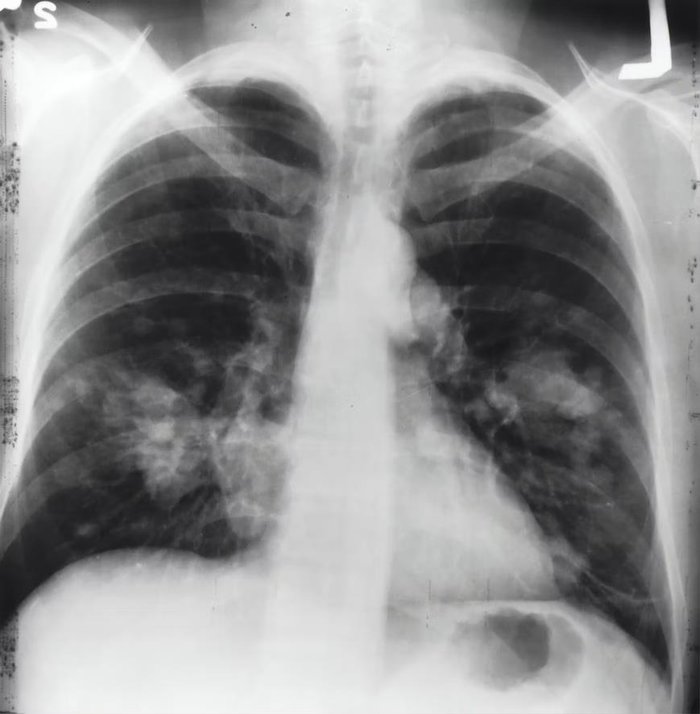

KOAH NEDİR? | Akciğer hastalığı olarak bilinen ve solunum yoluyla akciğerlere alınan oksijenin dışarı verilememesi olarak basitçe ifade edilebilen Koah hastalığı, günümüzün en sık rastlanan rahatsızlıkları arasında yer alıyor. Öldürücü boyutlara ulaşabilen ve nefes alma güçlüğü nedeniyle yakalan kişinin yşaam kalitesini oldukça düşüren bu hastalığa dikkat çekmek amacıyla 15 Kasım Dünya Koah Günü ilan edilmiştir. Peki Koah hastalığı neden olur, belirtileri nelerdir? - Koah hastalığının tedavisi var mı, öldürür mü? İşte tüm merak edilenler...

KOAH kalıcı akciğer hasarı oluşuncaya dek genellikle belirtilere sebep olmaz. Ancak, belirtiler ortaya çıktıktan sonra, hastalığa neden olan sigara gibi faktörler ortadan kaldırılmazsa, zaman içerisinde sürekli olarak kötüleşir.

KOAH'ta oluşan akciğer hasarı bir defa meydana geldikten sonra iyileştirilebilir veya geri döndürülebilir değildir. Fakat yapılan tedaviler, hastalığın belirtileri hafifletilebilir, hastalığa bağlı komplikasyonlar ortadan kaldırılabilir veya hızlı seyreden hastalığın yavaşlamasına yardımcı olabilir.